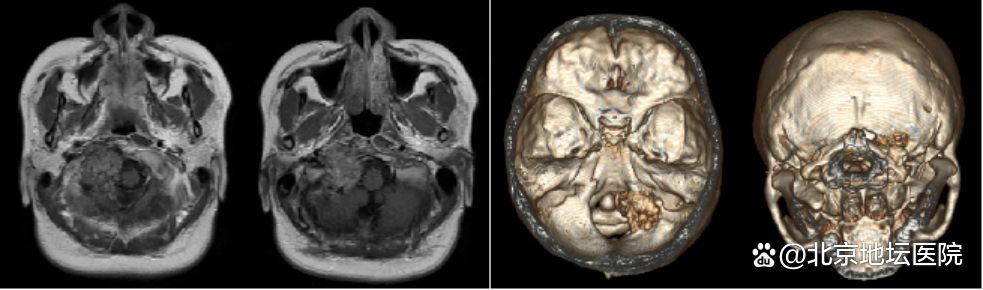

检查时,医生在小兰颈枕交界的枕髁区发现了一种少见的肿瘤,初步考虑是骨/软骨肉瘤,一种常见于儿童及青年长骨干骺端的原发性恶性肿瘤。这种肿瘤很少累计颅骨,而小兰的肿瘤则生长在头颈交界区(头部与脖子连接的区域),已经压迫到了椎动脉以及后组颅神经,引起了她的伸舌右偏以及声音嘶哑。考虑到手术切除肿瘤可能会影响头部稳定性,严重的话甚至可能危及生命。小兰选择暂缓手术、留下自己的孩子,等待分娩结束后再行手术治疗。

十月怀胎,一朝分娩,小兰生下了一个健康的宝宝,可难题又来了。因为小兰的肿瘤位于颅底、位置较深。已经严重破坏了枕髁区的骨质,与供应脑干的血管边界不清。术中将面临肿瘤切除困难、颅神经损伤、椎动脉破裂大出血以及颈枕部不稳定等多重困难。

术后第二天,小兰已经可以下地活动和正常进食了,咳嗽反射也表现良好。术后复查头CT、MRI及颈部平片示术区无出血、肿瘤完整切除;枕颈固定装置位置及颈椎曲度均良好。